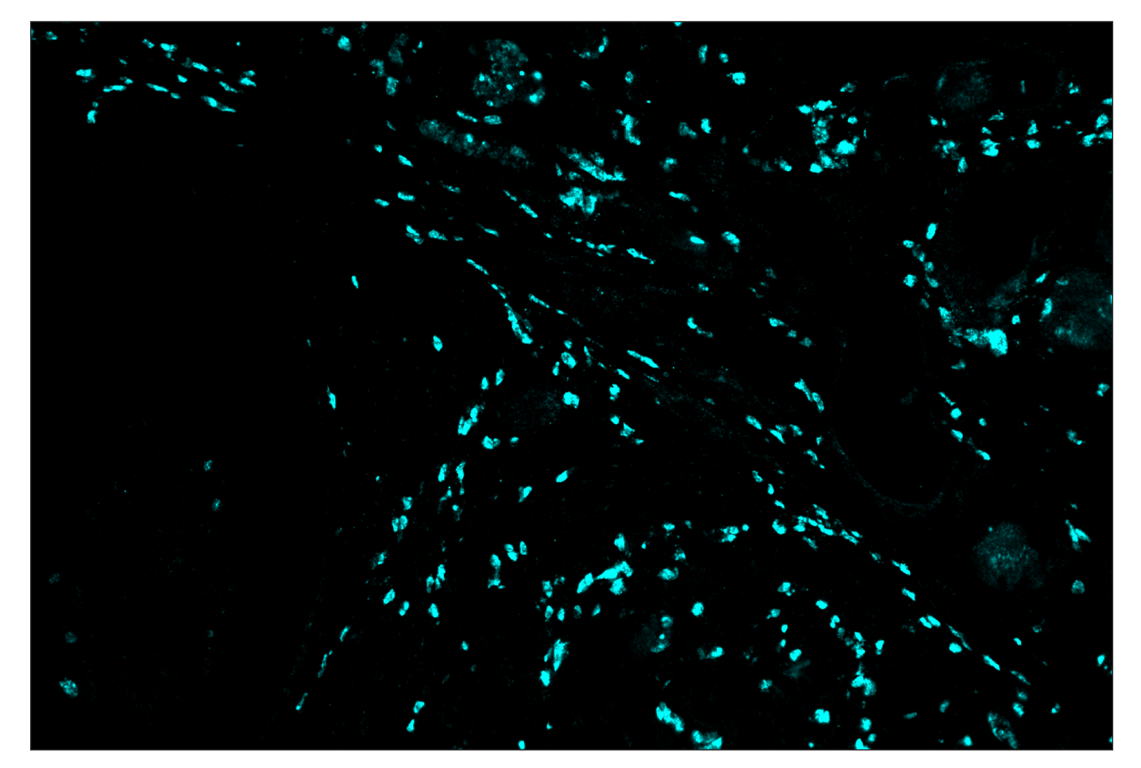

Immunohistochemistry Image 4: Arginase-1 (D4E3M) & CO-0075-750 SignalStar<sup>™</sup> Oligo-Antibody Pair

SignalStar™ multiplex immunohistochemical analysis of paraffin-embedded human gastric adenocarcinoma using Arginase-1 (D4E3M) & CO-0075-750 SignalStar™ Oligo-Antibody Pair #97934 (cyan). All fluorophores have been assigned a pseudocolor, as indicated. Staining was performed on the BOND RX autostainer by Leica Biosystems.